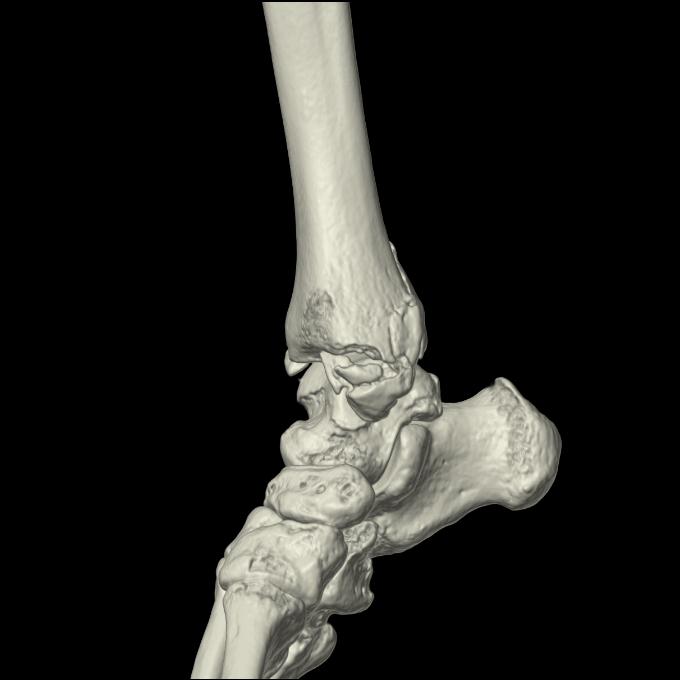

102755 1/4 2R 1/15 2R 右足関節 68歳女性 右三果脱臼骨折

103177 3/11 右足 2R 3/16 右足 2R リスフラン脱臼 55歳男性